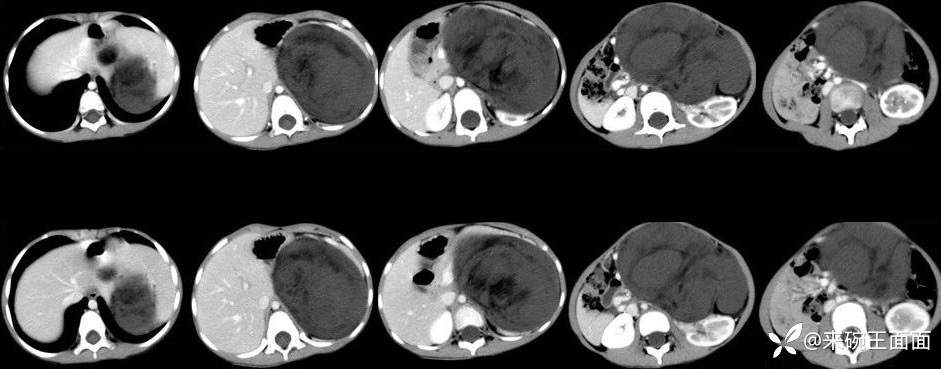

[现病史]1月余前无明显诱因发现左上腹肿物,无发热,无呕吐,无腹痛、腹泻、排便困难及其他不适,无尿频尿急,至当地医院CT示左上腹巨大占位性病变。【体格检查]腹膨隆,未及胃肠型及蠕动波,未及腹壁静脉曲张,腹软,左上腹可及大小约10*10cm肿物,质中,位置固定,无压痛、反跳痛,肝脾肋下未及,移动性浊音阴性,肠鸣音4-5次/分。

左上腹巨大软组织肿块影,密度混杂,边界清楚,其内可见脂肪密度,增强扫描未见强化。